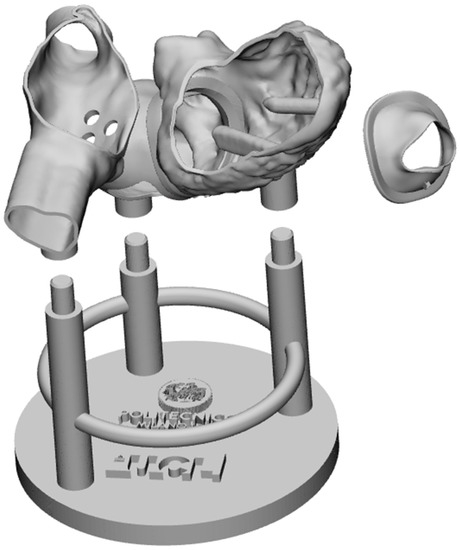

2.2.3. System Modularity

2.3. 3D Printing and Assembling